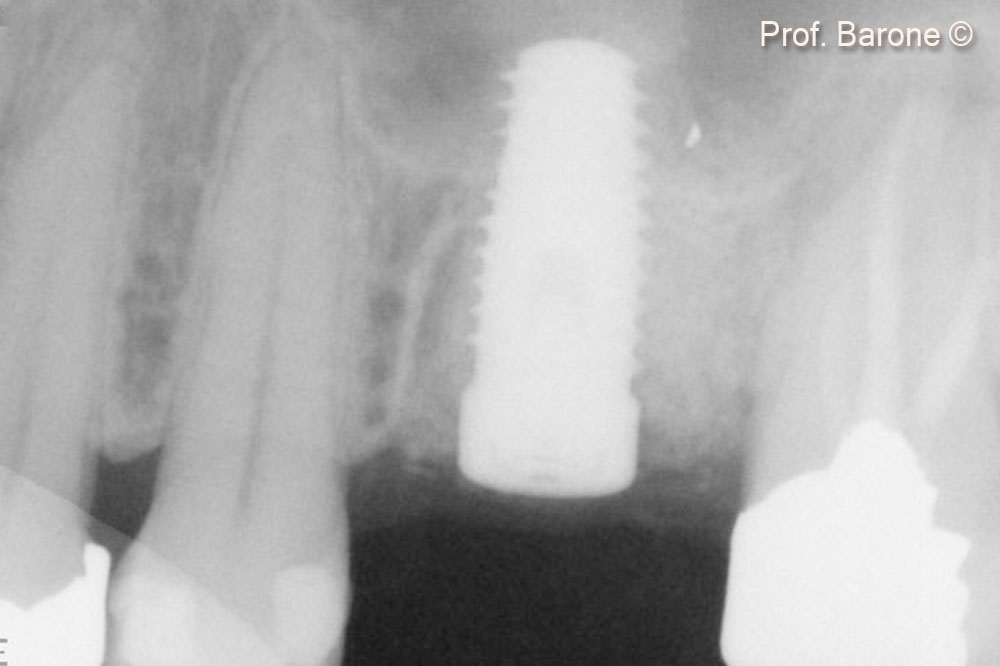

Hình ảnh X-quang quanh chóp răng ngay sau khi cấy ghép implant